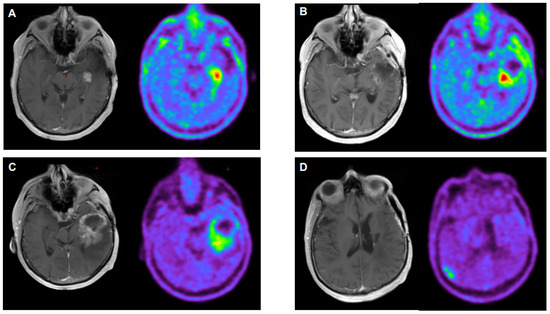

- Maurer, G.D.; Brucker, D.P.; Stoffels, G.; Filipski, K.; Filss, C.P.; Mottaghy, F.M.; Galldiks, N.; Steinbach, J.P.; Hattingen, E.; Langen, K.J. 18F-FET PET Imaging in Differentiating Glioma Progression from Treatment-Related Changes: A Single-Center Experience. J. Nucl. Med. 2020, 61, 505–511. [Google Scholar] [CrossRef] [PubMed]

- Galldiks, N.; Dunkl, V.; Ceccon, G.; Tscherpel, C.; Stoffels, G.; Law, I.; Henriksen, O.M.; Muhic, A.; Poulsen, H.S.; Steger, J.; et al. Early treatment response evaluation using FET PET compared to MRI in glioblastoma patients at first progression treated with bevacizumab plus lomustine. Eur. J. Nucl. Med. Mol. Imaging 2018, 45, 2377–2386. [Google Scholar] [CrossRef]

- Galldiks, N.; Rapp, M.; Stoffels, G.; Fink, G.R.; Shah, N.J.; Coenen, H.H.; Sabel, M.; Langen, K.J. Response assessment of bevacizumab in patients with recurrent malignant glioma using [18F]Fluoroethyl-L-tyrosine PET in comparison to MRI. Eur. J. Nucl. Med. Mol. Imaging 2013, 40, 22–33. [Google Scholar] [CrossRef]

- Galldiks, N.; Langen, K.J.; Holy, R.; Pinkawa, M.; Stoffels, G.; Nolte, K.W.; Kaiser, H.J.; Filss, C.P.; Fink, G.R.; Coenen, H.H.; et al. Assessment of treatment response in patients with glioblastoma using O-(2-18F-fluoroethyl)-L-tyrosine PET in comparison to MRI. J. Nucl. Med. 2012, 53, 1048–1057. [Google Scholar] [CrossRef]